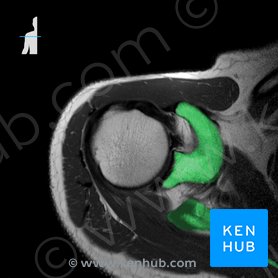

Refers to person place thing quality etc. The following categories include medical Spanish phrases for healthcare professionals in a variety of situations. Cross-sectional anatomy can be reconstructed in several planes.

Medical CT abbreviation meaning defined here. Computed tomography CT scanning is an extremely common imaging modality in modern medicineWith advancements in technology it is rapidly replacing many diagnostic radiographic procedures. Get the top CT abbreviation related to Medical.

The term computed tomography or CT refers to a computerized x-ray imaging procedure in which a narrow beam of x-rays is aimed at a patient and quickly rotated around the body producing signals that are processed by the machines computer to generate cross-sectional imagesor slicesof the body. Radiology instructions - CT scan MRI. Medical Spanish for healthcare providers.

Computed Tomography CT is a non-invasive diagnostic procedure that uses a series of x-rays to show a cross-sectional view of the inside of the body. Spanish nouns have a gender which is either feminine like la mujer or la luna or masculine like el hombre or el sol. O Physical Examination Terms.